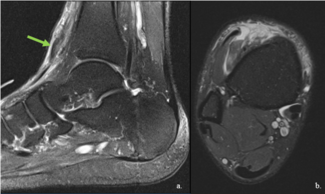

Kyle W. Abben, DPM, FACFAS; Kristen M. Brett, DPM; Danielle Nack, DPM

Tibialis anterior tendon rupture is rare but can lead to chronic pain if neglected. These authors discuss a surgical technique that can help patients regain dorsiflexory strength at the ankle joint without the need for post-op AFOs.